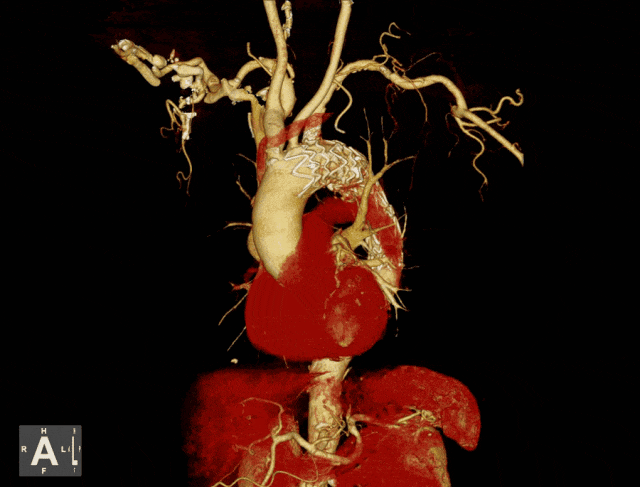

明确诊断后,宋主任立即关系九院血管外科大家刘光主任,为吴爷爷制定诊治决策,由于基础疾病较多,随即运行MDT多学科诊治样式,在奉城病院血管外科的引颈下,呼吸科、麻醉科、DSA等科室全力联接。

手术在刘光主任的指引下,由宋菊民、张荣、郭信大夫在全麻下进行,历经1小时30分钟,仅在患者右股动脉有一个穿刺点,左手臂留有一个细小切口。

置入支架,危机祛除